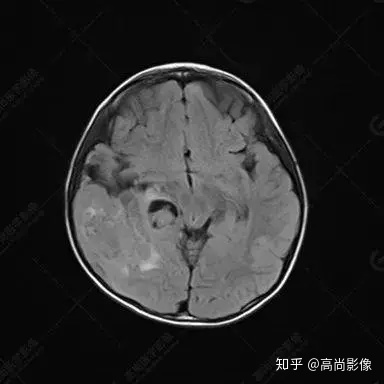

右側(cè)顳葉腫瘤切除術(shù)后(具體不詳):右側(cè)顳部骨質(zhì)不連續(xù)呈術(shù)后改變,右側(cè)顳葉術(shù)區(qū)見片狀長T1長T2信號影,F(xiàn)LAIR呈低信號;術(shù)區(qū)后方右側(cè)顳枕葉見一巨大占位性病變影,邊界欠清,大小約6.2×5.8×4.3cm(前后×左右×上下),信號不均勻,T1WI呈等稍低信號間雜少許高信號,T2WI呈高稍低混雜信號,DWI示部分病灶彌散受限,相應(yīng)ADC圖減低,磁敏感序列見部分呈極低信號,增強(qiáng)掃描可見明顯不均勻強(qiáng)化,鄰近硬腦膜及小腦幕增厚并明顯強(qiáng)化;另延髓右前方及右側(cè)橋小腦角區(qū)見一不規(guī)則形異常信號影,大小約3.2×1.3×3.7cm(左右×前后×上下),呈長T1稍長T2信號,F(xiàn)LAIR呈等信號,DWI未見受限,增強(qiáng)后明顯均勻強(qiáng)化,鄰近腦膜明顯強(qiáng)化。鄰近腦實質(zhì)及右側(cè)顳角明顯受壓;左側(cè)大腦半球未見局灶性信號異常,中線結(jié)構(gòu)稍左移。

右側(cè)顳葉腫瘤切除術(shù)后:現(xiàn)術(shù)區(qū)后方右側(cè)顳枕葉及延髓右前方占位,右側(cè)顳枕部硬腦膜及小腦幕明顯強(qiáng)化,結(jié)合既往影像資料,考慮為胚胎源性惡性腫瘤,如非典型畸胎樣/橫紋肌樣瘤(AT/RT)或原始神經(jīng)外胚層腫瘤(PNET)。

非典型畸胎樣/橫紋肌樣瘤(AT/RT) 是一種高度惡性中樞神經(jīng)系統(tǒng)腫瘤,臨床罕見,臨床表現(xiàn)無特異性,好發(fā)于 5 歲以下兒童,尤以 3 歲以下多見,在兒童原發(fā)性中樞神經(jīng)系統(tǒng)(CNS)腫瘤中占 1%~3%。該腫瘤體積一般較大,幕上大于幕下,有明顯的占位效應(yīng)。該腫瘤成分復(fù)雜,囊變、出血、壞死常見。因此 AT/RT信號混雜,囊性部分呈 T1WI低、T2WI高信號,增強(qiáng)后不強(qiáng)化;若瘤體出血,囊內(nèi)可見T1WI稍高信號、T2WI低信號,實性部分在 T1WI上呈混雜等、低信號,在T2WI 及 T2-FLAIR上呈混雜等高信號,增強(qiáng)掃描后大部分呈環(huán)形條帶樣明顯強(qiáng)化,中心壞死區(qū)不強(qiáng)化。另外,該腫瘤實性成分在DWI上呈高信號,說明腫瘤細(xì)胞核密集,水分子擴(kuò)散明顯受限,提示該腫瘤惡性程度高,容易復(fù)發(fā)及轉(zhuǎn)移。